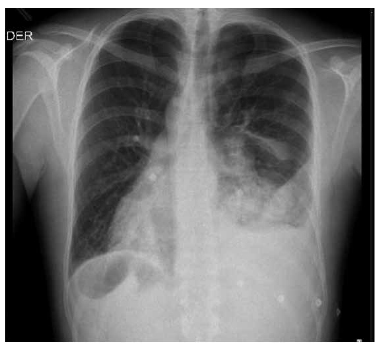

Hombre de 23 años con antecedente de asma y sinusitis a repetición desde la infancia; consulta por cuadro clínico de una semana consistente en dolor pleurítico en hemitórax izquierdo asociado a disnea y tos productiva con expectoración mucoide. Al ingreso taquicárdico, desaturado, con presencia de sibilancias espiratorias ocasionales en ambos campos pulmonares, sin signos de dificultad respiratoria. Paraclínicos de ingreso, con trastorno leve de la oxigenación sin trastorno ácido base y sin hiperlactatemia, hemograma con leucocitosis más neutrofilia, función renal y hepática normales, dímero D elevado (Tabla 1) Radiografía de tórax de ingreso con presencia de infiltrados intersticiales gruesos parahiliares bilaterales con área de opacidad alveolar confluente en lóbulo inferior izquierdo, con derrame pleural y signos de pérdida de volumen con retracción del hemidiafragma y atelectasia parcial de la língula, mas hallazgo incidental de dextrocardia (Fig. 1 ); debido a lo anterior se inicia cubrimiento antibiótico empírico con piperacilina tazobactam 4.5 gramos intravenoso cada 6 horas.

Figura 1 Radiografia de tórax: infiltrados intersticiales gruesos parahiliares bilaterales con área de opacidad alveolar confluente en lóbulo inferior izquierdo, con derrame pleural y signos de pérdida volumen con retracción del hemidiafragma y atelectasia parcial de la língula, mas hallazgo incidental de dextrocardia